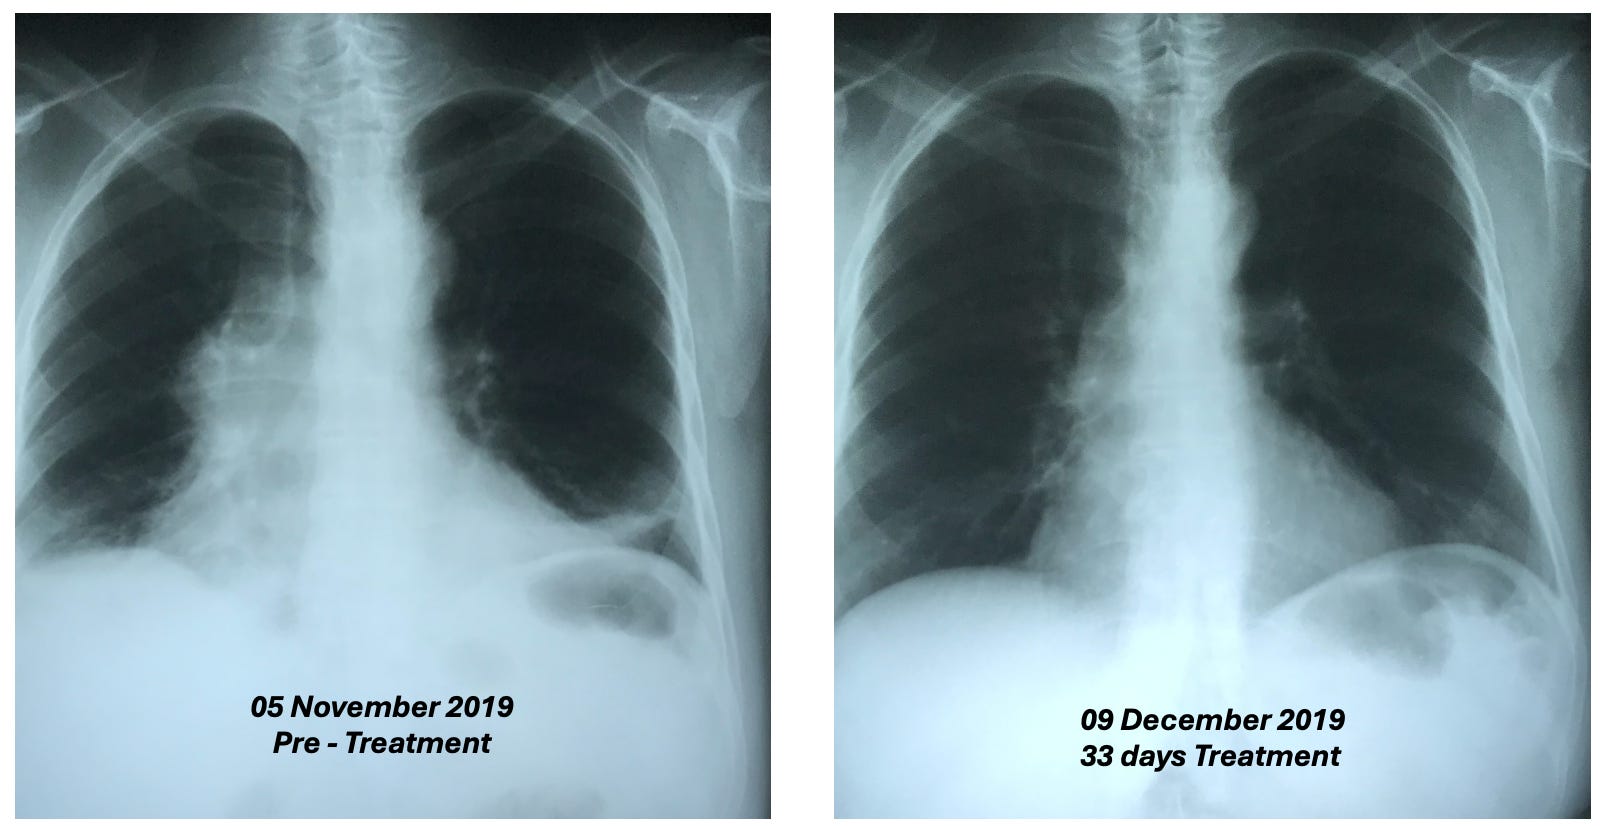

•A 55-year-old female who had a mediastinal tumor (type unknown as it was wrapped 560° around the aorta and hence could not be biopsied) which fully resolved after 33 daily D-hematoxylin treatments.

Additionally, this was the CT prior to treatment where the tumor can be seen around the aorta:

While this was the CT two weeks following the D-hematoxylin treatment:

Lastly, at five years follow up, there was no recurrence.